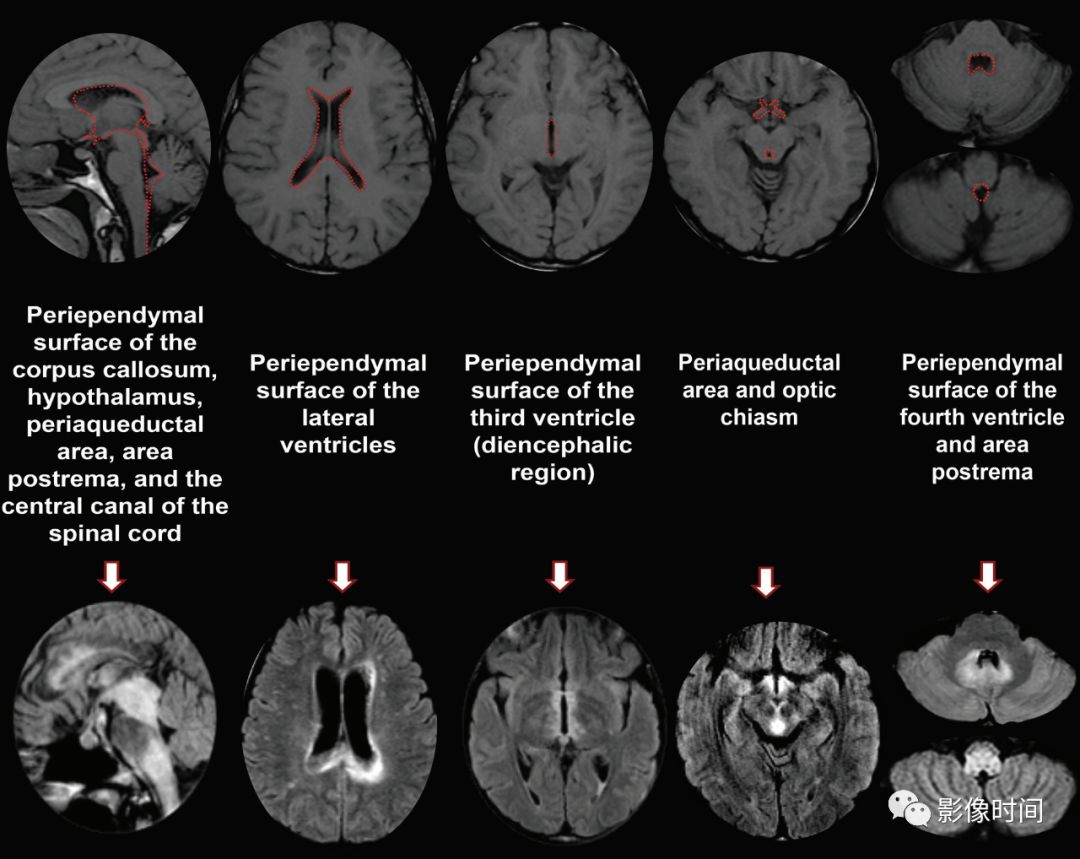

神经脊髓炎谱系疾病(neuromyelitis optica spectrum disorder,NMOSD):是一种由水通道蛋白-4(AQP-4)自身抗体介导的炎性脱髓鞘疾病,青年或中年女性较多见,临床常为双侧视神经炎和脊髓炎导致失明和截瘫,也可累及大脑。

MRI:

脊髓:病灶 T2WI 呈高信号,T1WI 呈稍低信号,急性期出现斑片状或云雾状强化,轴位常位于脊髓中央,长度>3 个椎体长度。亮点征:轴位 T2WI 很高信号的多发斑点,信号高于脑脊液,特异性=97%。

病灶分布于脊髓中央,长度大于3个椎体,亮点征

大脑:AQP4 通道是中枢神经系统最丰富的水通道,在室管膜周围、下丘脑和软脑膜下区以及脑干、极后区均有高表达。因此,高表达 AQP4 的特定区域成为 NMO 自身免疫靶点